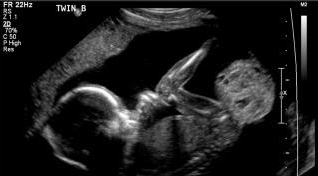

Các dấu hiệu và triệu chứng của u quái vùng cùng cụt phụ thuộc vào kích thước và vị trí của khối u. Một số khối u có thể được chẩn đoán trước sinh bằng phương pháp siêu âm.

Theo đó, bụng mẹ lớn bất thường là dấu hiệu hay gặp đầu tiên gợi ý thai nhi có khối u. Kích thước tử cung lớn hơn bình thường có thể do khối u lớn hoặc do đa ối. Các biểu hiện ít gặp hơn bao gồm tiền sản giật ở mẹ. U vùng cùng cụt thai nhi có thể ở dạng nang, dạng đặc hoặc dạng hỗn hợp trên hình ảnh siêu âm. Hình ảnh mật độ không đồng nhất của khối u có thể do vùng hỗn hợp của khối u hoại tử, thoái hóa nang, xuất huyết hoặc canxi hóa.

Là một trong những khối u hiếm gặp nhưng bệnh có thể phát hiện sớm từ quý 1 thai kỳ bằng phương pháp siêu âm chẩn đoán dị tật thai nhi. Theo đó, việc chẩn đoán sớm có ý nghĩa vô cùng quan trọng để thai nhi có cơ hội theo dõi, phẫu thuật đốt laser cắt đứt mạch nuôi làm kích thước khối u nhỏ đi, đem lại tiên lượng sống tốt cho trẻ.